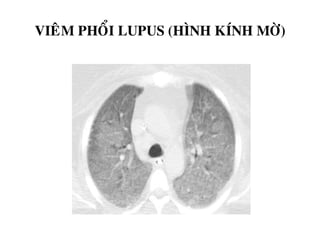

VIEÂM PHOÅI LUPUS (HÌNH KÍNH MÔØ)

DAÏNG KÍNH MÔØ

-Ñaùm môø nheï, khoâng xoùa môø maïch maùu trong vuøng

-Phuø phoåi, vieâm phoåi, xuaát huyeát phoåi…